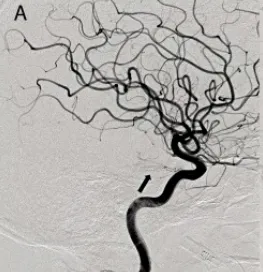

1、常规二维血管造影

在手术开始前,患者已经签署了正式的知情同意书。随后,在全身麻醉的状态下,对患者实施了脑血管造影检查。

通过常规的二维血管造影技术,观察到由左侧颈内动脉(internal carotid artery,ICA)虹吸部的垂直段供血的肿瘤染色并不显著。

另外,肿瘤周围的动脉存在明显的占位效应,这种效应主要影响了左侧大脑后脉(PCA)和脉络膜动脉(SCA)。